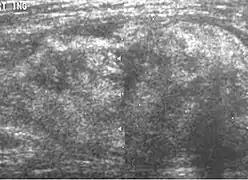

Medical imaging

Medical ultrasonography and magnetic resonance imaging (MRI) of liposarcomas are helpful and often essential in determining their extent, surgical accessibility, and relationship to any observed organ dysfunctions. Since ultrasonography is usually unable to distinguish a liposarcoma from a benign lipoma, MRI is the initial imaging of choice to provide evidence relative to making this distinction.[67]

Fig. 5 Ultrasonography of a liposarcoma with high-echo areas reflected from its lipomatous matrix and low-echo areas reflected from its non-lipomatous areas.[69]

Fig. 5 Ultrasonography of a liposarcoma with high-echo areas reflected from its lipomatous matrix and low-echo areas reflected from its non-lipomatous areas.[69] Fig. 6 Ultrasonography of a liposarcoma mimicking a lipoma. This homogeneous high-echoic mass has the same appearance as a lipoma.[69]